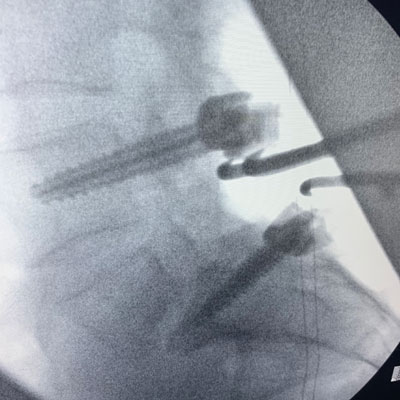

Figure 2 – Fluoroscopic sagittal and AP images demonstrating post-pedicle screw placement at L4 and S1.